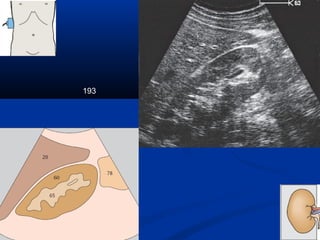

193